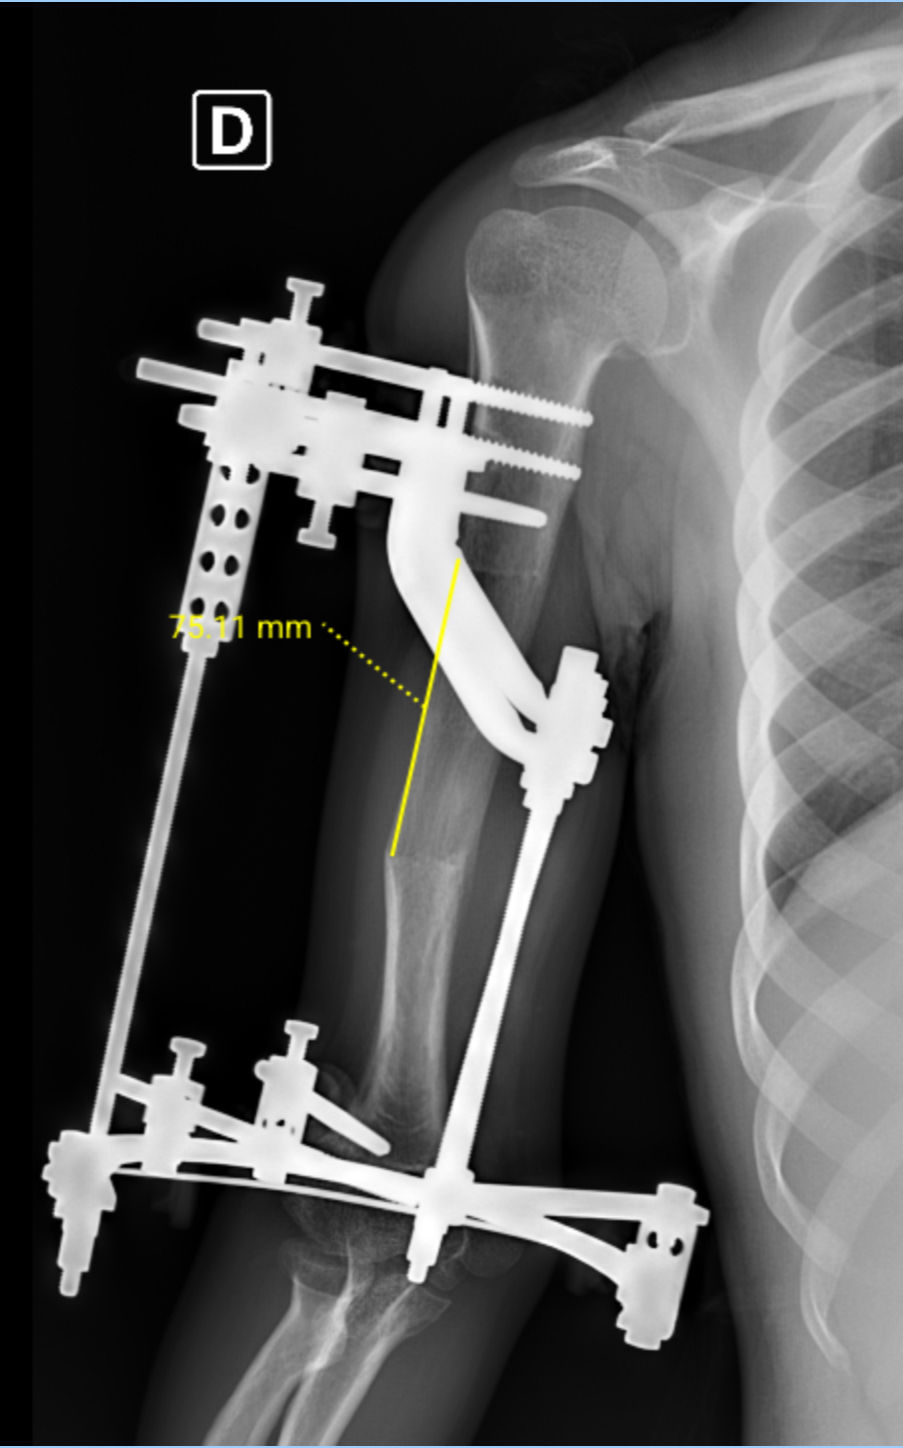

Técnica de alongamento ósseo com fixador externo sobre haste intramedular (LON)

LON  Lenghtening over nail / Alongamento ósseo sobre haste

O que é o LON?

É uma técnica de alongamento em que se combina, no mesmo tratamento, um fixador externo (por curto período) e uma haste intramedular bloqueada por dentro do osso. A ideia é usar o fixador apenas para “abrir” gradualmente o osso (distração) e usar a haste para estabilizar o membro durante e após o alongamento, encurtando o tempo com pinos e arcos na pele. Estudos e revisões apontam que o LON reduz o tempo de fixador externo e melhora o controle do eixo em relação ao uso do fixador externo isolado.

Passo a passo do LON

Veja as etapas Planejamento e seleção do caso 1. Avaliação clínica e radiológica, planejamento do eixo e da quantidade de alongamento; discussão de metas, riscos e reabilitação. 2. Cirurgia – fase inicial – Realiza-se uma corticotomia (osteotomia) em local planejado. – Introduz-se uma haste intramedular bloqueada no canal do osso (fêmur ou tíbia). – Monta-se um fixador externo (ex.: Ilizarov ou LRS) com os pinos percutâneos posicionados fora do trajeto da haste. Essa combinação simultânea é chamada de “fixação híbrida”.  3. Latência (início da cicatrização) – Período curto após a cirurgia (tipicamente ~1 semana) antes de começar a distração, permitindo a formação inicial do calo ósseo. 4. Distração (o “alongamento” propriamente dito) – O paciente/ equipe faz giros programados no fixador externo, várias vezes ao dia, para separar as metades do osso em ritmo baixo e constante (em protocolos clássicos, cerca de ~1 mm/dia, ajustado à idade, osso e qualidade do regenerado). – Fisioterapia ativa desde o início para manter mobilidade e alongar músculos/tecidos.  5. Retirada do fixador externo e consolidação com a haste – Quando se atinge o comprimento planejado e o osso novo está evoluindo bem, o fixador externo é removido. – A haste é bloqueada com novos parafusos e continua oferecendo estabilidade interna enquanto o osso “amadurece” e calcifica até consolidar completamente. Isso reduz muito o período com pinos na pele.